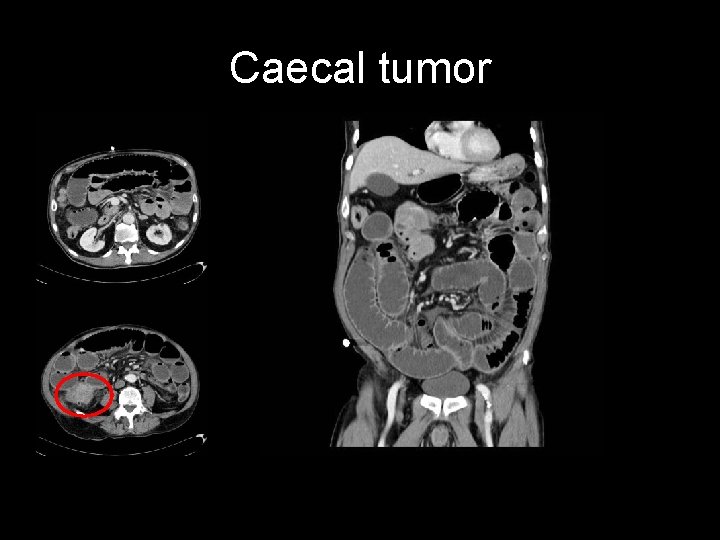

Caecal tumor